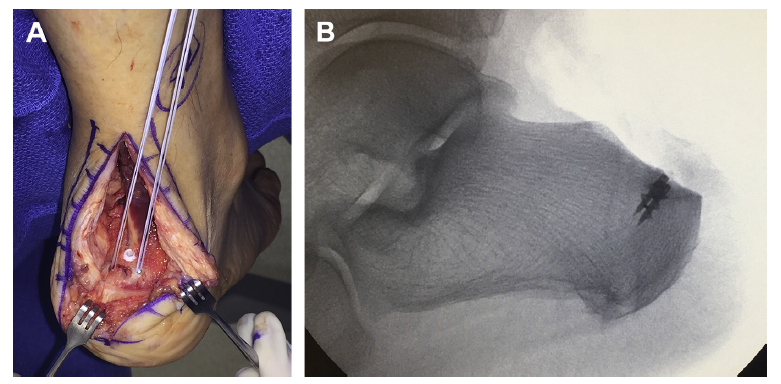

开放外侧手术入路

后正中入路

外侧入路切除跟骨内侧骨膜比较困难,采用正中劈开跟腱入路行 Haglund 畸形切除术联合跟腱止点重建术,取得了良好疗效

118个病人,并发症发生率为14%,都是较小的并发症,75%为感染,经治疗后好转。1/3的病人存在穿鞋不适,大多数因为瘢痕所致。也是造成病人满意度不好的唯一因素。

关节镜下手术可以减少并发症、缩短住院时间,病人满意度高,可以在门诊完成。关节镜下手术和中间跟腱劈开入路在手术效果和病人满意度方面无明显差异。